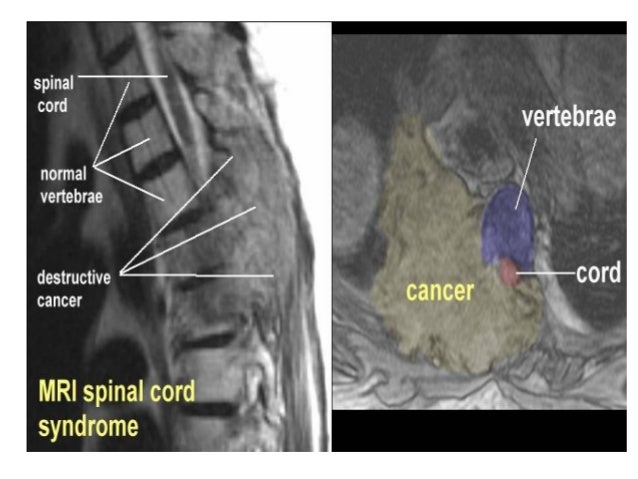

Compression of the spinal cord is due

predominantly to extradural metastases

(95%) and usually results from tumor

involvem...

MRI